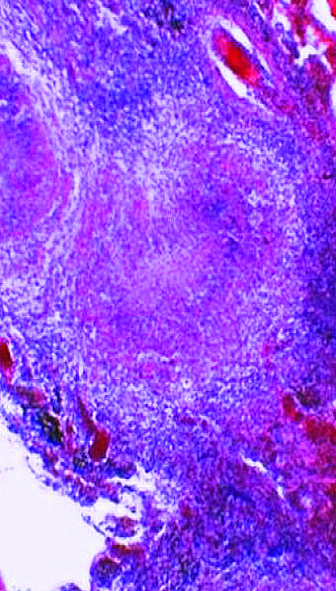

Для подострого диссеминированного туберкулёза лёгких, развивающегося при гематогенном рассеивании микобактерий, характерна субтотальная очаговая диссеминация с преимущественной локализацией очаговых теней в верхних и средних отделах лёгких. Очаговые тени в основном крупные (5-10 мм), малой или средней интенсивности (субтотальная крупная равноочаговая диссеминация), обычно с нечёткими контурами (рис. 18-27). Некоторые очаговые тени сливаются и образуют фокусные затемнения с участками просветления, обусловленными распадом лёгочной ткани. Иногда деструктивные изменения представлены тонкостенными кольцевидными тенями.

Рис. 18-27. Подострый диссеминированный туберкулёз. а - фрагмент обзорной прямой рентгенограммы; б - КТ.